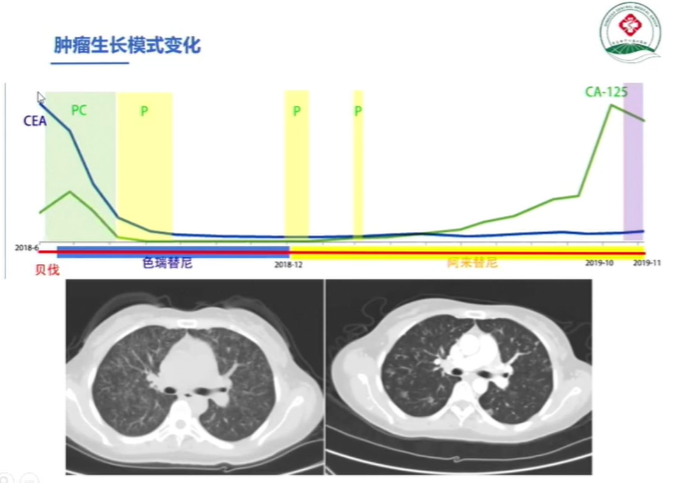

接下来,看一例其中的具体治疗案例患者基本信息

辅助检查情况如下

一线治疗方案:

在经过两轮治疗后患者病情进展后进行测序

但遗憾的是患者未能找到有效的驱动突变,因此在这样情况下考虑到ALK抑制剂仍然对患者有获益,后线治疗方案如下

在经过一段时间治疗后,患者出现治疗分离反应

(其颅内转移灶处于大PR状态,但肺部病灶从散点状变成弥漫状态)

在确认患者进展后,我们进行了进展病灶的穿刺并进行基因检测,发现了包括ALK融合CRKL、MAPK3等多靶点的突变。

其中通过文献查阅,我们倾向于患者的MAPK通路被激活是主要的耐药机制之一,因此在ALK抑制剂的基础上,我们大胆使用了二甲双胍后续又替联合了曲尼司特以及双硫仑。最终患者的治疗过程如下

但经过一段时间的治疗之后患者依然进展,因此我们再次选择CRKL通路作为治疗方向。查阅文献发现相关药物——西达本胺有相关临床研究。

患者在经过两个周期的治疗后显示PR,然而由于后续患者拒绝治疗,无法进一步获得后续数据。